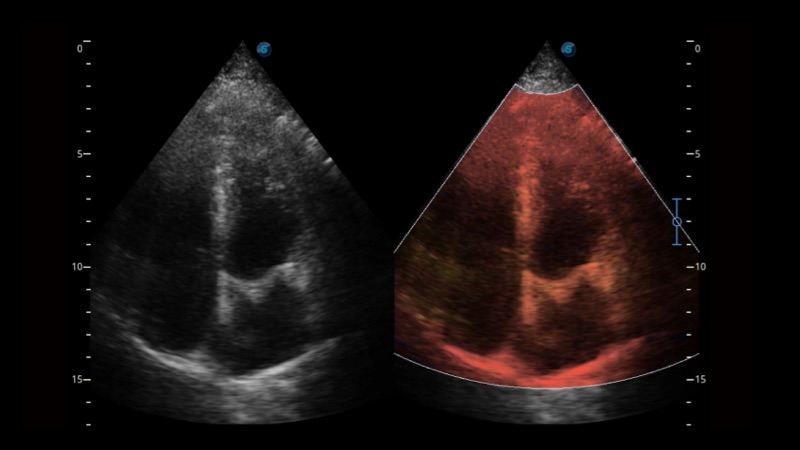

SR Flow高分辨率血流成像

高分辨率血流成像技术提高了对低速血流信号的检测能力。在提高空间分辨率的同时,也克服了血流外溢现象,为用户提供更加真实的血流动力学信息。